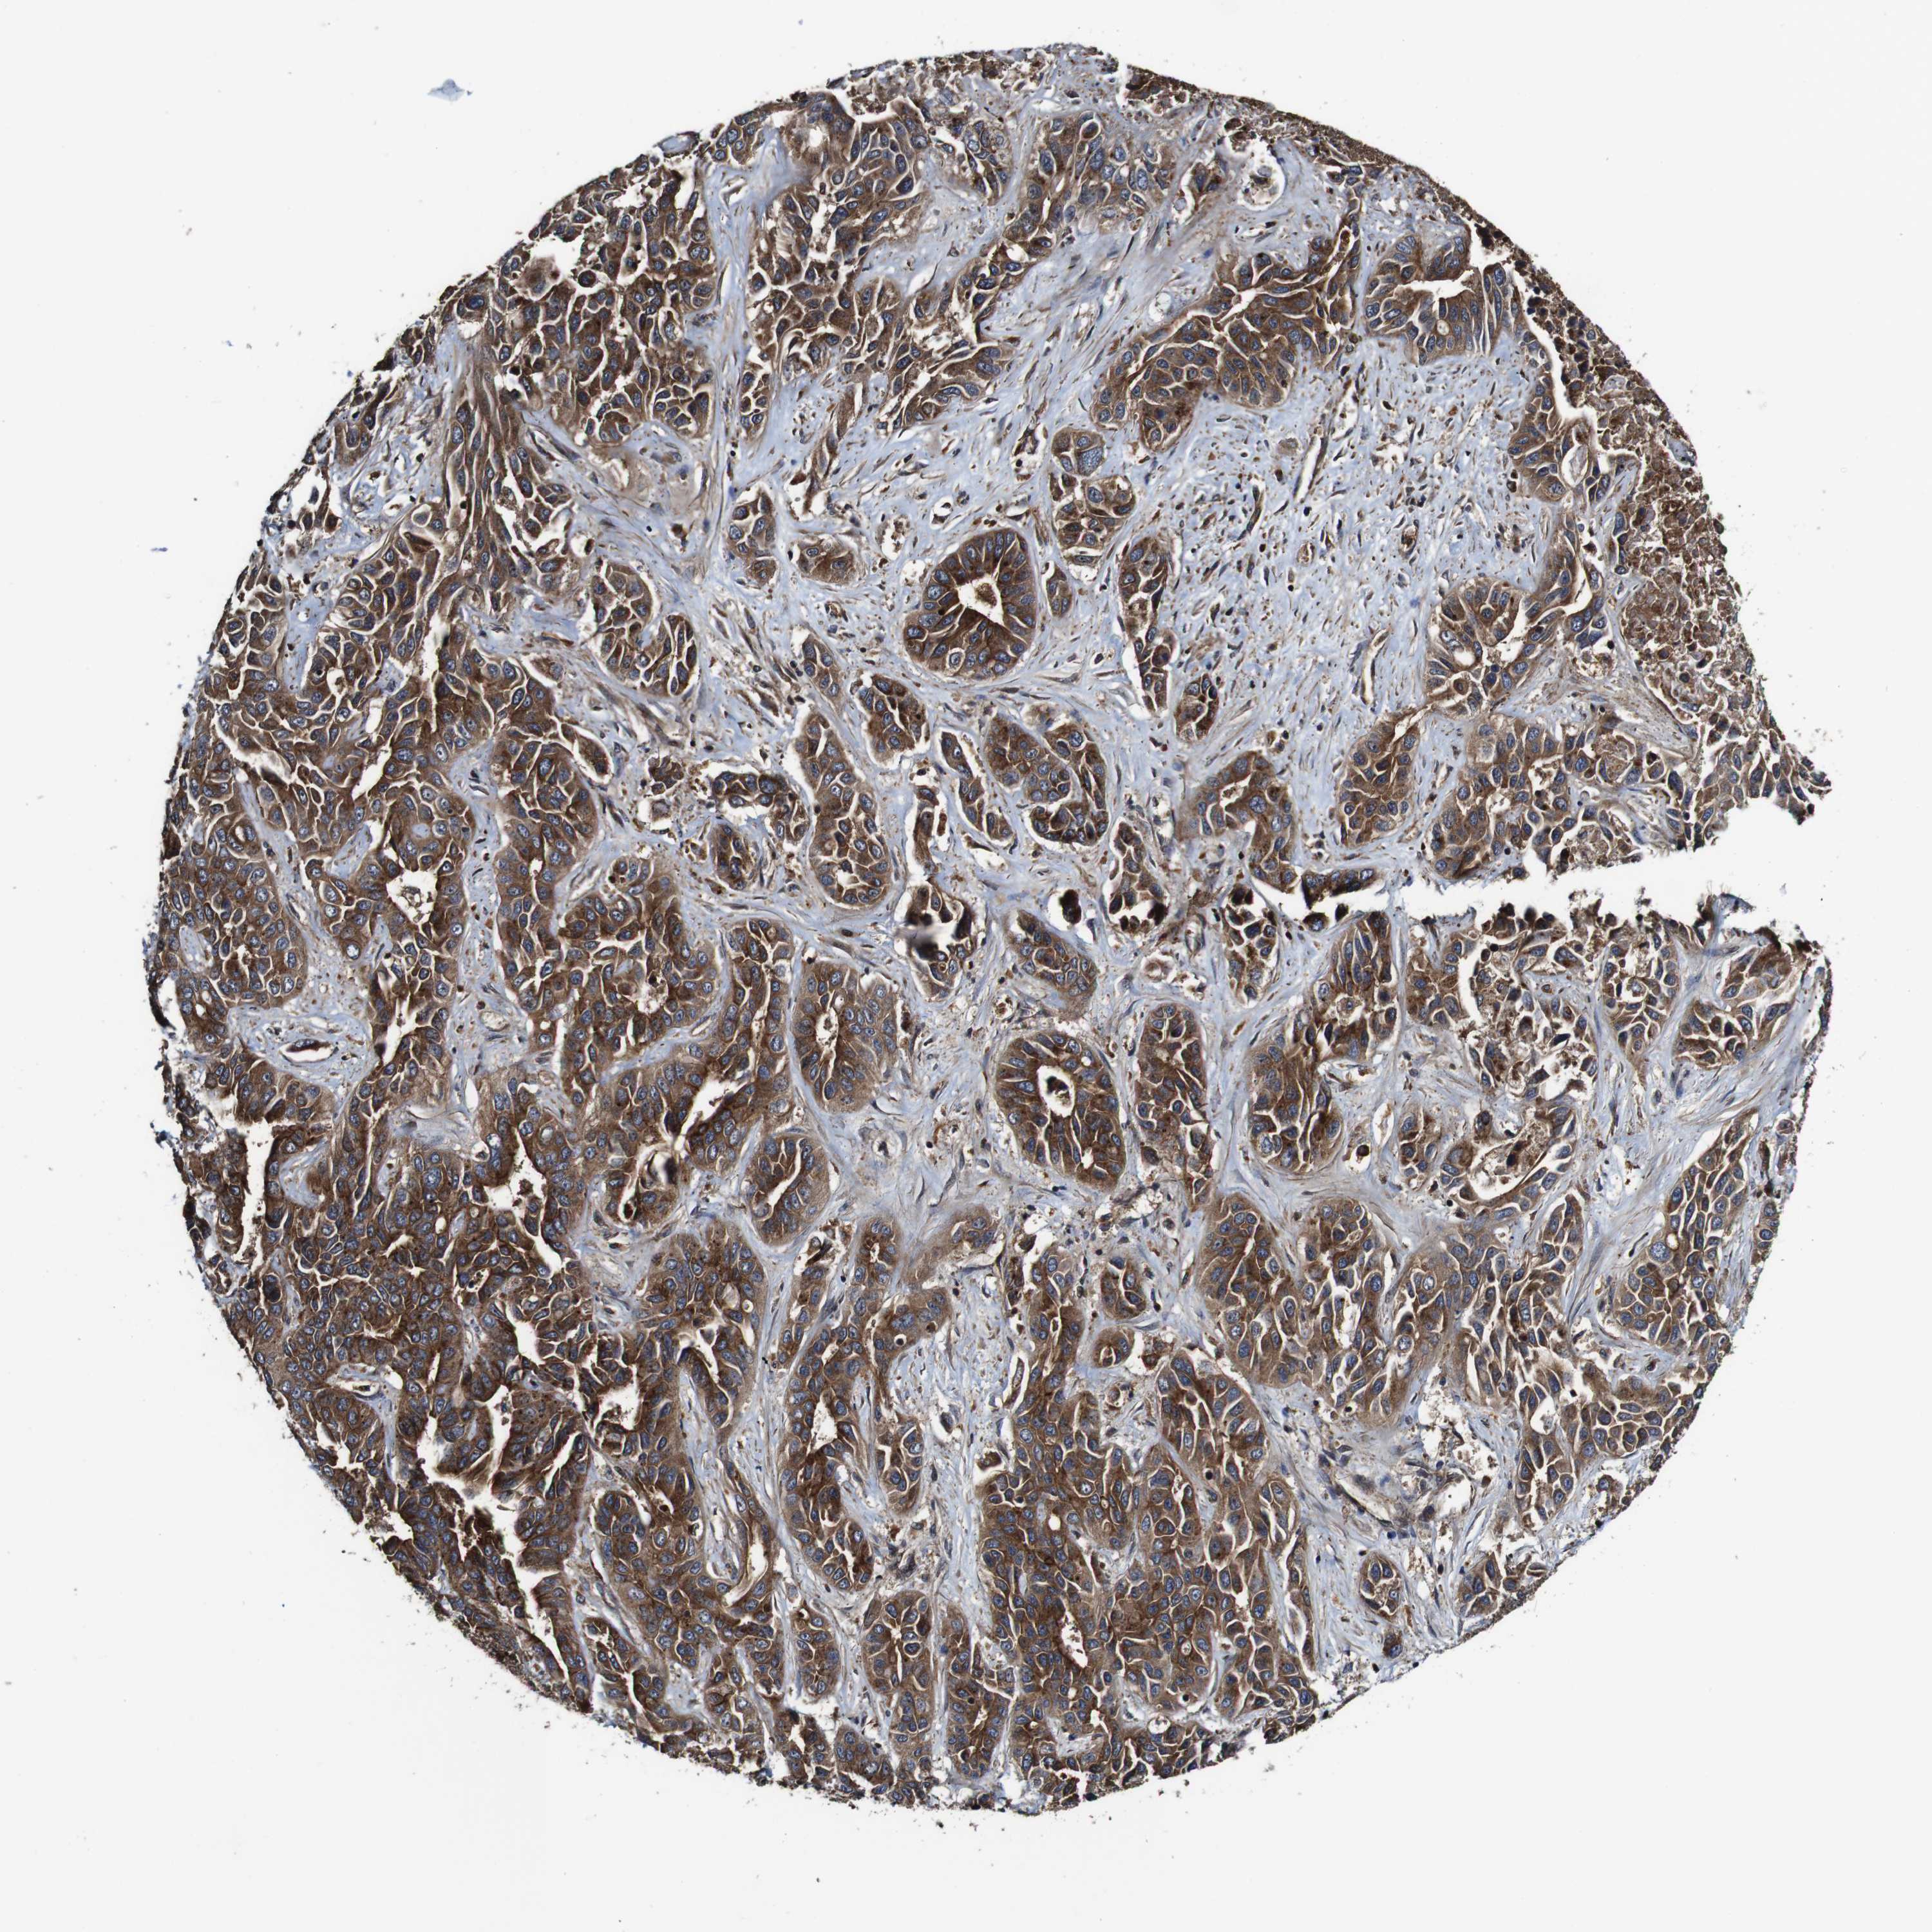

LIVER CANCER - Protein expressioni

A mouse-over function shows sample information and annotation data. Click on an image to view it in a full screen mode. Samples can be filtered based on level of antibody staining by selecting one or several of the following categories: high, medium, low and not detected. The assay and annotation is described here.

Note that samples used for immunohistochemistry by the Human Protein Atlas do not correspond to samples in the TCGA dataset.

Antibody stainingi

Antibody staining in the annotated cell types in the current human tissue is reported as not detected, low, medium, or high, based on conventional immunohistochemistry profiling in selected tissues. This score is based on the combination of the staining intensity and fraction of stained cells.

Each image is clickable and will lead to virtual microscopy that enables deeper exploration of all samples and also displays staining intensity scores, fraction scores and subcellular localization as well as patient and tissue information for each sample.

Antibody HPA012128

Antibody HPA012297

Staining

High

Medium

Low

Not detected

Intensity

Strong

Moderate

Weak

Negative

Quantity

>75%

75%-25%

<25%

None

Location

Nuclear

Cytoplasmic/membranous

Cytoplasmic/membranous,nuclear

Cholangiocarcinoma

Carcinoma, Hepatocellular, NOS